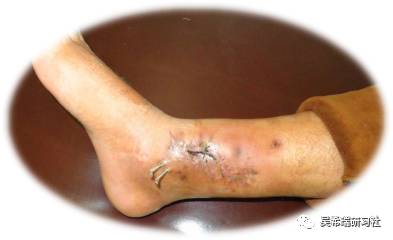

病例6

TIPS:尽量不要跨关节固定水泥对肌腱有保护作用肌腱表面可以有肉芽生长接受游离植皮治疗过程中预防足下垂